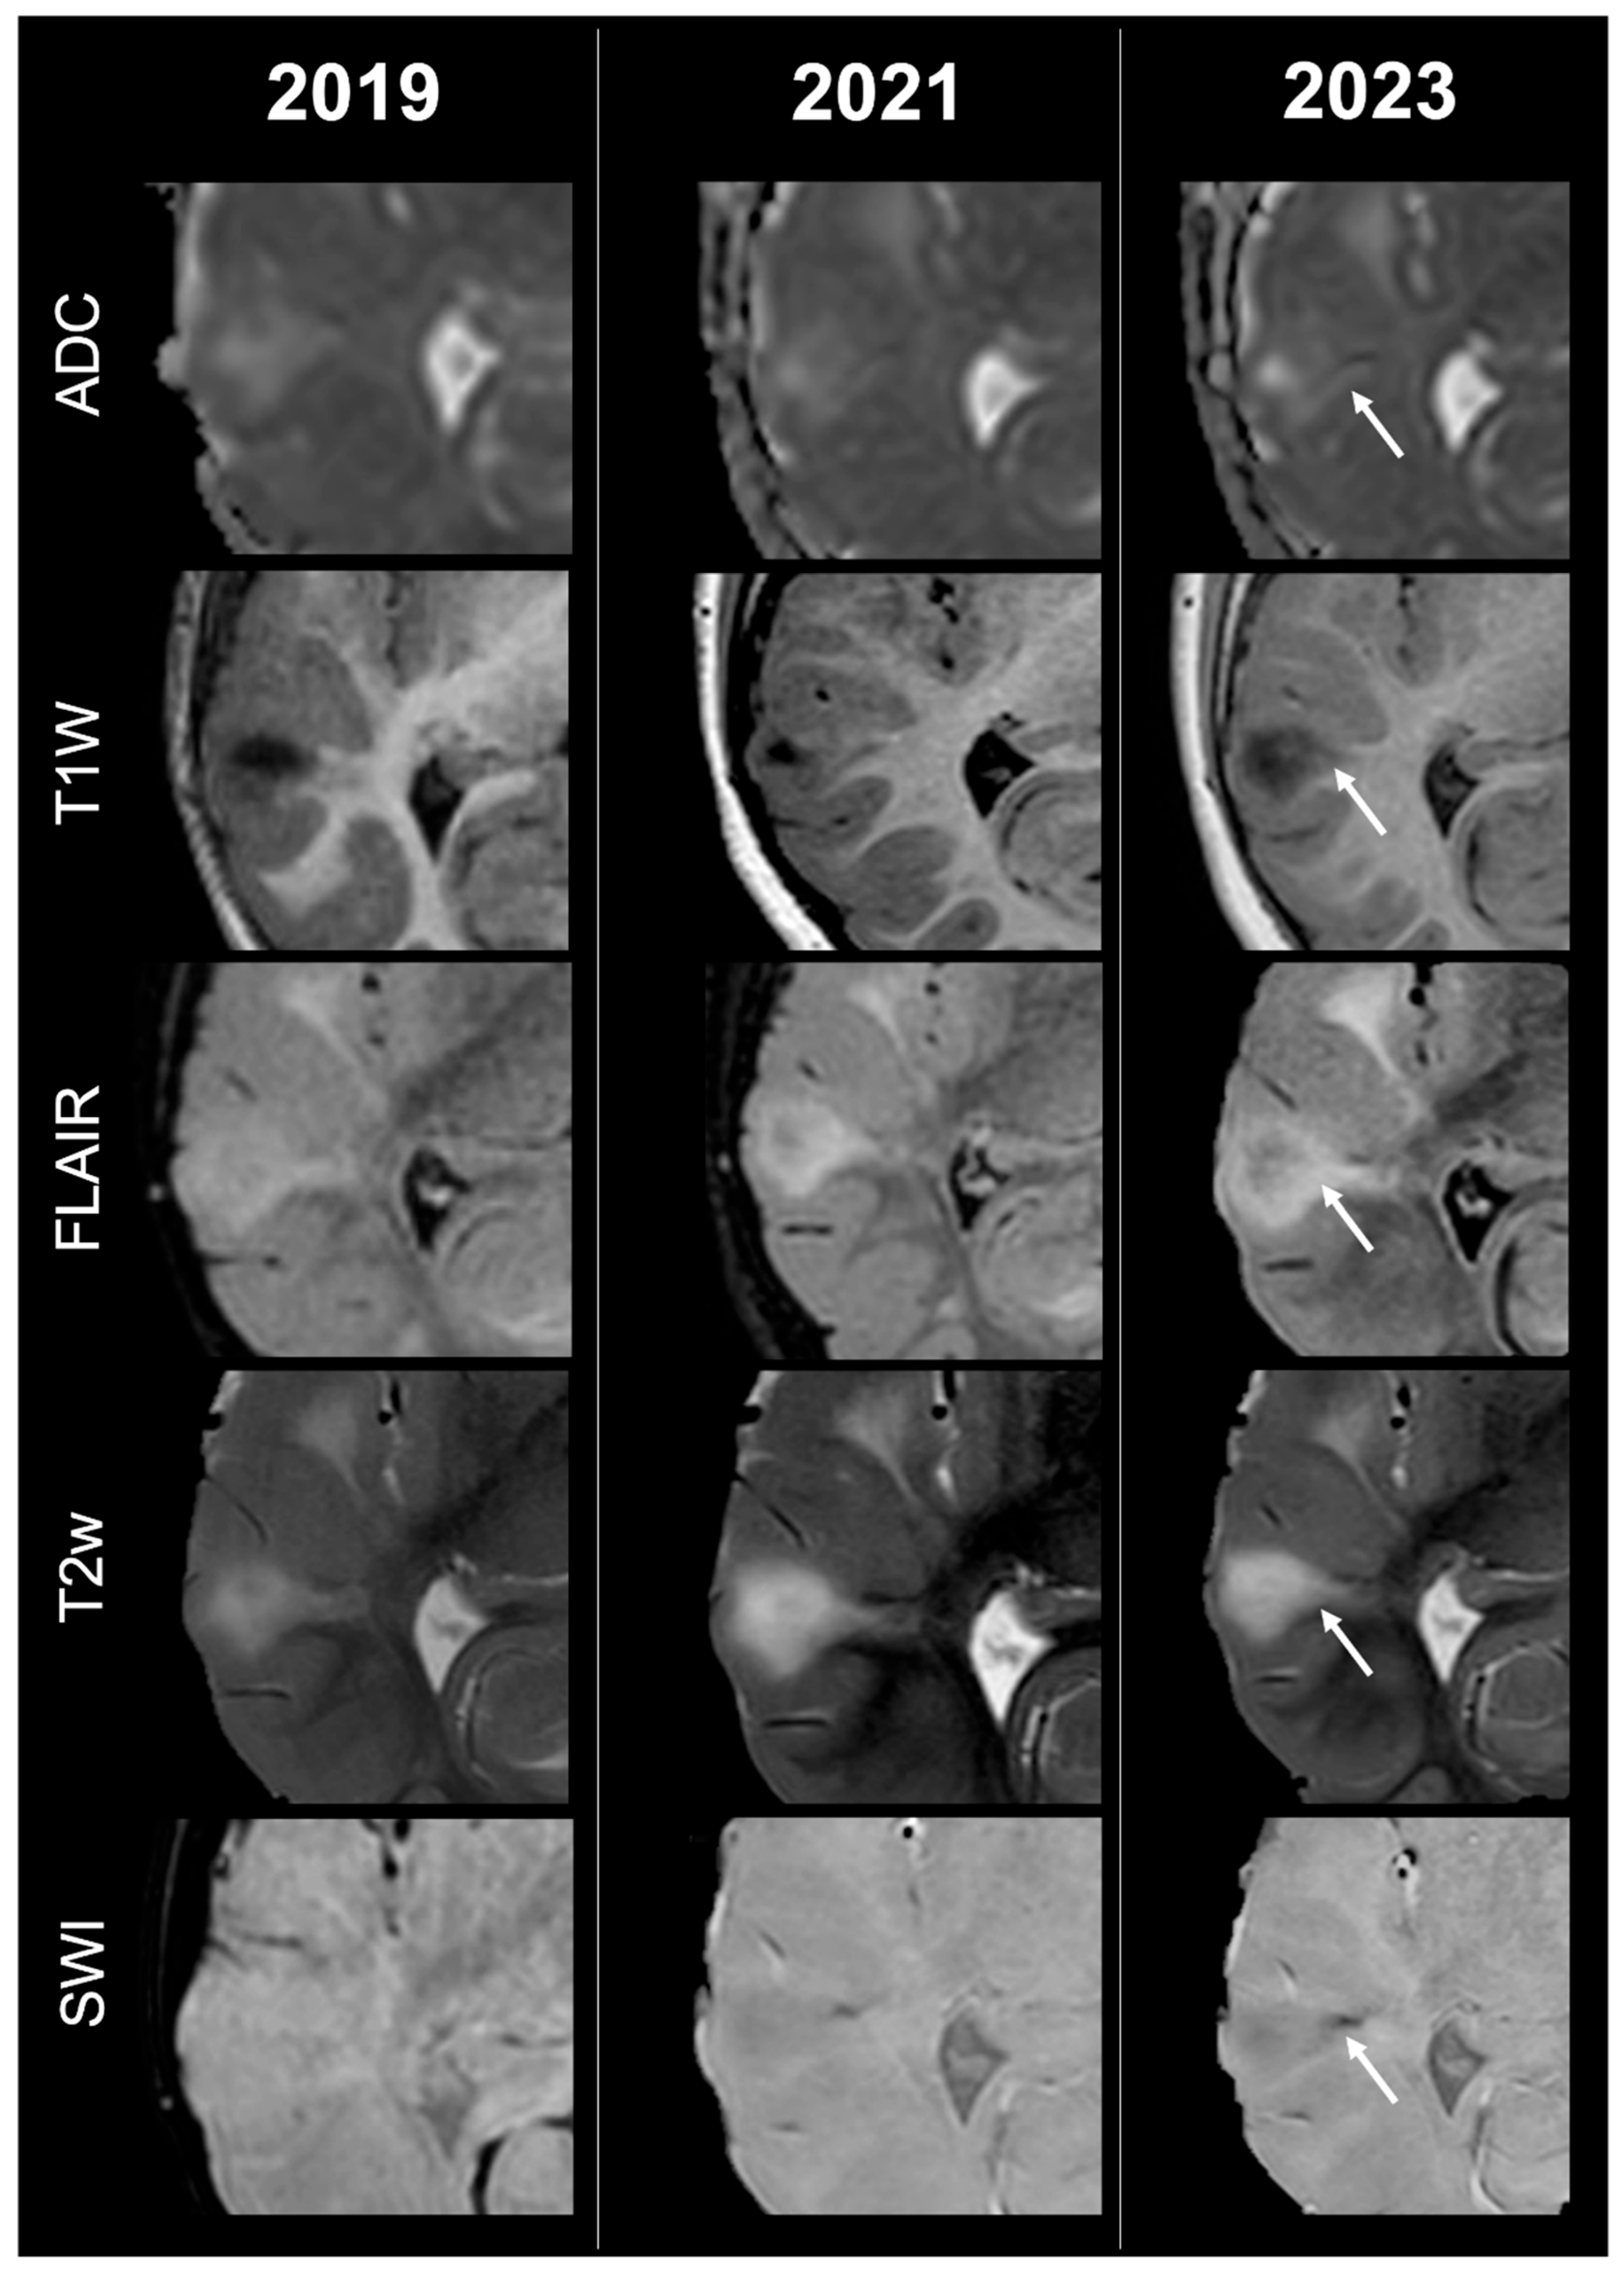

Figure 2.

Right temporal tuber transition from type B to C1 at three different timepoints in a male patient diagnosed with TSC2.

Concerning total lesion count, the interobserver agreement was excellent, with an ICC of 0.91 (95% CI: 0.87–0.95). At baseline, the total number of CTs identified across the cohort was 918 (mean ± SD = 16.1 ± 12.4), whereas at the last available MRI follow-up, the overall count increased to 1070 (mean ± SD = 18.8 ± 13.3), corresponding to a net gain of 152 CTs, equal to a relative variation of +17%. When stratified by tuber type, distinct trajectories were observed over time. Type A CTs, which were relatively abundant at diagnosis (N = 303, mean ± SD = 5.3 ± 7.0), decreased to 255 (mean ± SD = 4.5 ± 5.9) at follow-up, yielding a reduction of 48 lesions (−16%). Conversely, type B CTs showed an opposite trend, increasing from 438 (mean ± SD = 7.7 ± 8.4) at baseline to 556 (mean ± SD = 9.8 ± 8.6) at follow-up, corresponding to a net increase of 118 tubers (+27%). An example of MRI signal evolution from tuber A to tuber B is shown in Figure 1. Similarly, type C1 CTs rose from 160 (mean ± SD = 2.8 ± 4.8) to 220 (mean ± SD = 3.9 ± 5.8), with a net gain of 60 tubers (+38%). Type C2 CTs, initially rare at diagnosis (N = 14, mean ± SD = 0.2 ± 0.8), markedly expanded to 33 (mean ± SD = 0.6 ± 1.5), accounting for an increase of 19 CTs (+136%). Finally, type D CTs were only sporadically encountered, with a modest increase from 3 (mean ± SD = 0.1 ± 0.3) to 6 (mean ± SD = 0.1 ± 0.4), equating to a 100% variation. The observed increment of type C2 tubers was attributable almost exclusively to the progressive transformation of pre-existing type B lesions and, more prominently, type C1 lesions, while the increase in type C1 tubers reflected the gradual conversion of both type A and type B CTs that were already detectable at disease onset. An example of MRI signal evolution from tuber B to C1 is shown in Figure 2, while from tuber C1 to C2 in Figure 3. Only in one patient was a type C1 tuber newly identified at follow-up without clear evidence at baseline. In contrast, newly apparent tubers emerging over time but not clearly visible on baseline scans were most frequently represented by type A and type B lesions. Type D tubers were rare overall and were identified in only six lesions from four patients with a particularly high lesion burden; in all but one case they represented the evolution of type A or type B CTs (an example of MRI signal evolution from tuber A to tuber D is shown in Figure 4), while in a single case they were associated with adjacent subtle calcific foci. Overall descriptive data are summarized in Table 1.